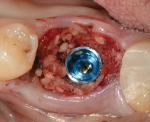

Selecting the proper diameter implant to be used for a molar site is very important.3 Traditionally, the width of an implant determined the forces it could withstand as well as the beginning point of its emergence profile. However, with the introduction of "platform switching" to many implant systems, the emergence profile of the restoration begins from the width of the implant connection and not the actual width of the implant.4 Consequently, a large imbalance between the width of the implant and the width of the connection results in a much narrower initial connection width, requiring the implant to be placed more apically to allow for the space needed to develop the proper emergence profile. Selecting the most appropriate implant connection size to relate to the mesio-distal and bucco-lingual dimensions of the tooth being replaced is imperative to long-term success.5 Therefore, placing an implant (eg, the authors use the NobelParallel Conical Connection WP implant; nobelbiocare.com) that is larger than 5 mm in diameter (eg, 5.5 mm in diameter) with a connection size that is also larger than 5 mm in diameter (eg, 5.1 mm in diameter) allows for greater force distribution and tolerances in molar sites. Furthermore, this allows for a much more ideal emergence profile to be developed (Figure 2).